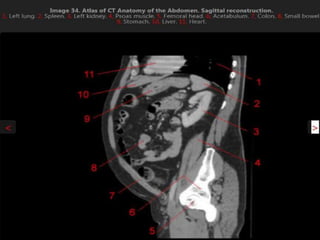

CT cross sectional anatomy.

CT – computedtomography. •Cross-sectional modality with capabilities for multiplanar reconstruction and dynamic imaging to assess vascularity •Tube rotates around the body and a circle of stationary detectors detects the penetrating x-rays forming an image.